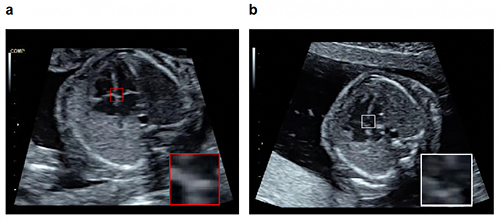

次にアノテーション済み正常データで学習した物体検知技術を用いて、検査対象の超音波画像から心臓の部位を検知します。物体検知技術は検査画像中からも人に近い精度で特定の部位を検知できます。したがって、物体検知によって得られた部位の検知状況と正常な心臓の部位の位置とを比較することによって、多少の陰影が入り込んだ不完全な検査画像であってもロバストな異常検知が実現されます。具体的には、以下の手順で異常を検知します(図1、特許出願中)。

図1 物体検知技術を活用した胎児心室中隔の異常検知例

正常胎児心臓(a)において映っているべき心室中隔を提示し(赤枠)、アノテーション済み教師データを用いて学習した物体検知技術を用いて、症例bにおいて実際に映っていた心室中隔の部位を検知する(白枠)。その相違から症例bは異常所見を有すると判定する(b.心室中隔欠損)。